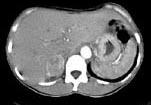

问题 女,35岁,上腹部隐痛不适伴消瘦1月,胃镜提示胃癌,CT扫描如图所示:右侧肾上腺区可见一占位性病灶,应诊断为 ( )

选项 A、右肾上腺嗜铬细胞瘤 B、右肾上腺错构瘤 C、右肾上腺腺癌 D、右肾上腺转移瘤 E、右肾上腺腺瘤

答案 D